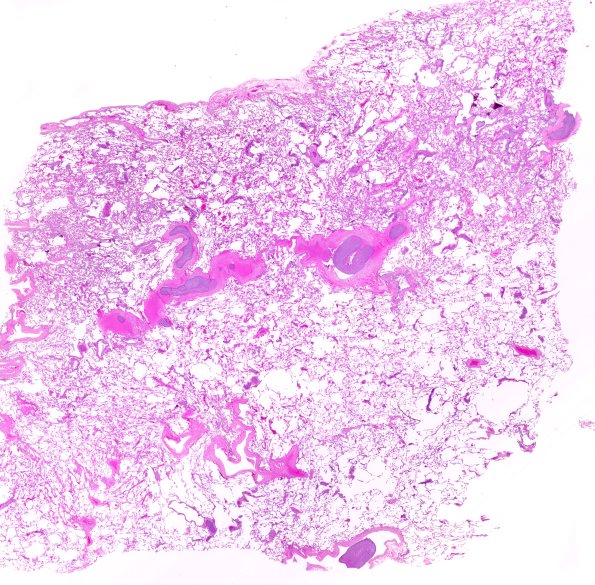

Infarct - Embolic

23C1 Lung emboli (Case 23) H&E 1FU1 WM

23C1,2 There are organizing thrombi and tumor emboli within the pulmonary vasculature involving both lungs. (H&E)